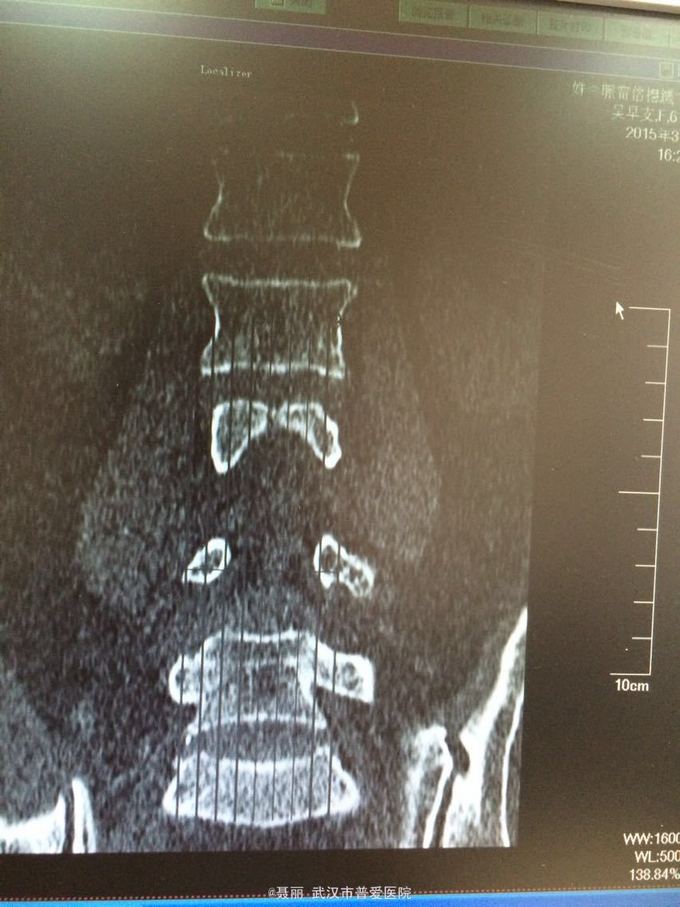

患者,女,61岁 因腰部疼痛,伴左下肢酸胀、疼痛、麻木5月余入院。 患者约5月前无明显外伤等诱因感腰腿疼痛不适,以腰部及左下肢为主,活动后左下肢疼痛加重,休息可缓解。 既往病史:既往体健,否认高血压、糖尿病等其他传染病史,否认食物药物过敏史。

辅助检查:2015年2月27号到我院拍腰椎MRI检查提示:L4椎体Ⅰ-Ⅱ度滑脱,腰椎退变。

初步诊断:腰椎滑脱症 治疗计划:1、完善相关检查:胸片、心电图,血常规,尿常规,肝肾功能电解质、术前全套 2,活血化瘀扩管治疗。卧床休息。 L4滑脱复位+L4/5椎间盘摘除、椎管减压+椎间cage3植骨融合术